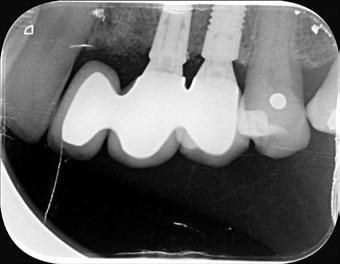

-Estudio radiográfico inicial (ortopantomografía y radiografías periapicales) (Figura 2).

Figura 2. Ortopantomografía inicial.